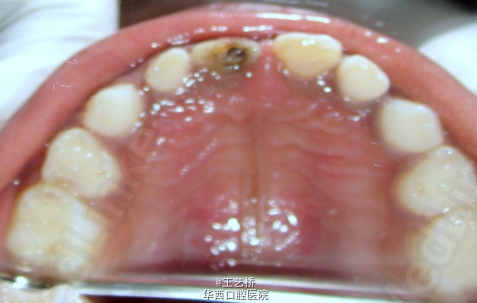

警惕孩子的不正常行为

小朋友对周围的一切事物难免会充满好奇,但是一旦出现不正常行为,大家就要警惕了。以下两个案例都是由于小朋友的不正常行为所造成的。